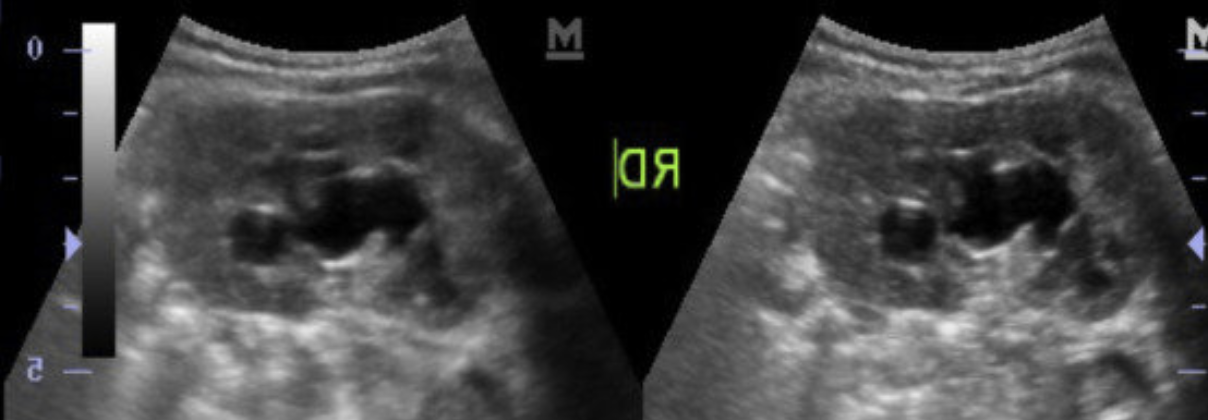

US

Hidronefrosis

Quistes renales